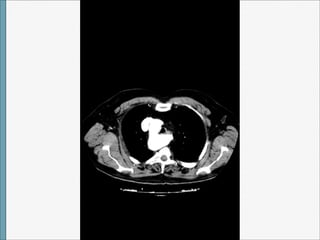

TAC

Arco Aórtico Derecho

1)CON ARTERIA SUBCLAVIA IZQUIERDA ABERRANTE

• Prevalencia:1/100. No predominio por sexo o

raza.

• Embriología: ruptura entre la arteria carótida

común izquierda y la arteria subclavia

izquierda que se origina sobre un divertículo

de Kommerell.

• Clínica: no sintomatología, hallazgo

incidental. Si presenta síntomas

relacionados con :

- Compresión esófago y tráquea por el

diverticulo o la arteria subclavia izquierda.

• -Persistencia de un ligamento arterioso

entre arteria subclavia aberrante y arteria

pulmonar.

• No relación con cardiopatía congénita